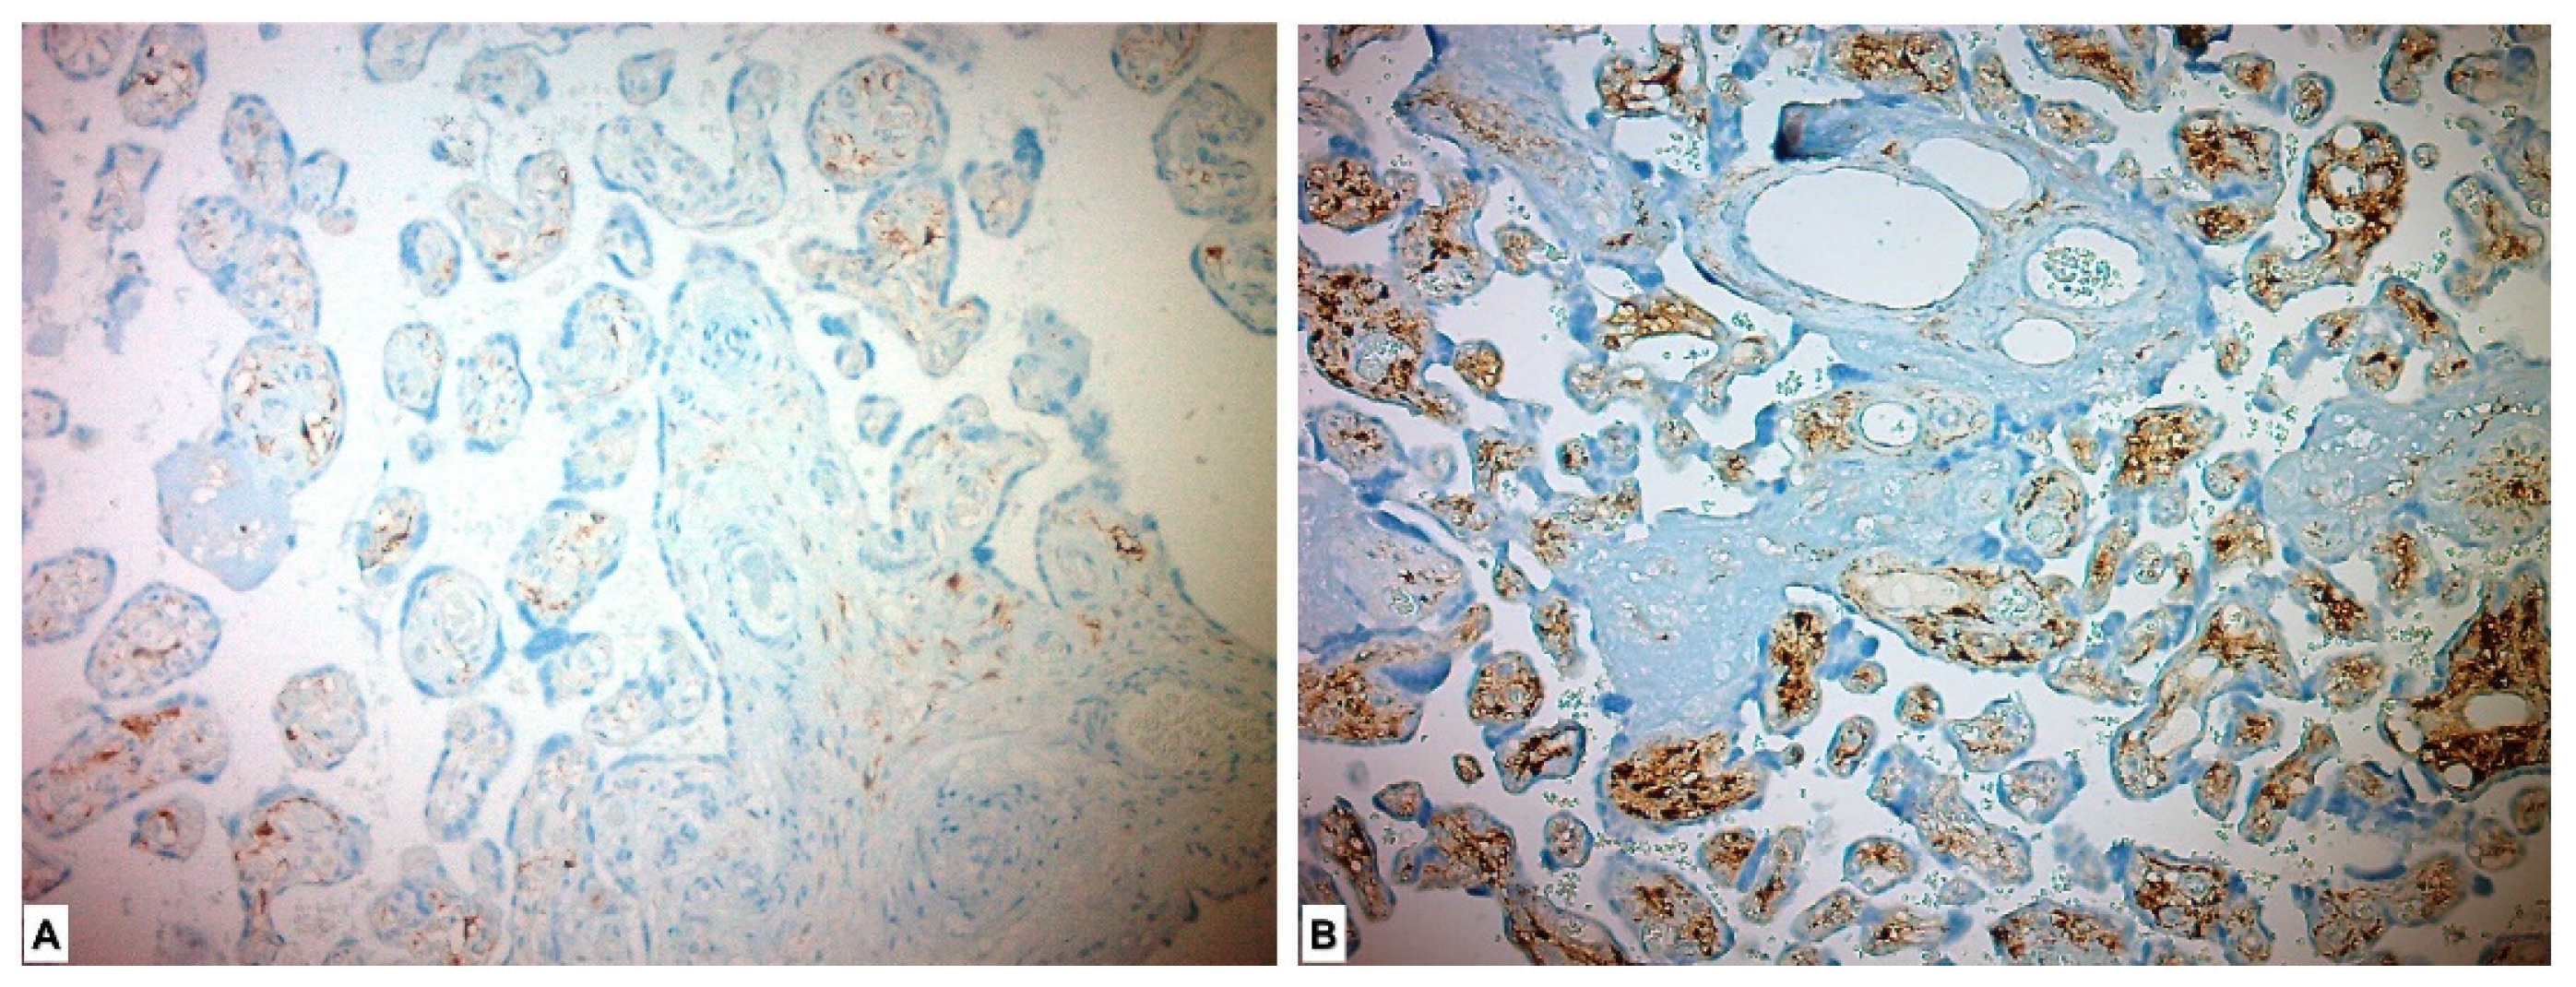

3.3. Immunohistochemical Results

| ADAM17 n (%) | <0.001 * | ||

| High Expression | 56 (100) | 0 | |

| Low Expression | 0 | 43 (100) | |